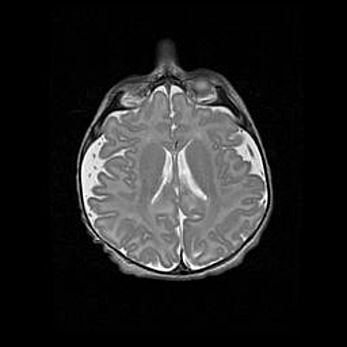

Церебральная ишемия II.

Возраст: 5 дней

Вес: 3400 г

Пол: женский

Окружность головы: 35 см

Срок гестации: 39 недель

Церебральная ишемия – это заболевание, характеризующееся недостаточностью (гипоксией) либо полным прекращением (аноксией) снабжения мозга кислородом по причине закупорки одного или нескольких сосудов. Это приводит к  что метаболическим расстройствам различной степени тяжести в тканях головного мозга, развитию коагуляционных некрозов и гибели нейронов.